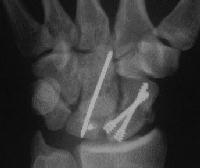

Case 8. Transscaphoid perilunate fracture dislocation...

Two screws put in dorsally, LT ligament reinforced with a strip of extensor retinaculum left attached to the triquetrium and anchored into the lunate; temporary capitolunate pin.

Click for larger image

Late, with asymptomatic partial union or nonunion, but no haloing.